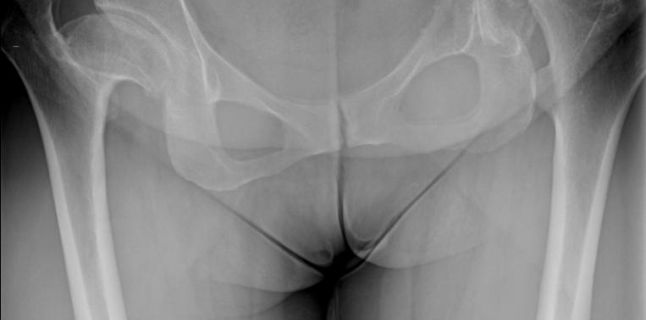

Prima interventie a constat in montarea a doua proteze in cazul unei paciente in varsta de 46 de ani, cu sold displazic bilateral care a insemnat inegalitate de membre, durere si dificultati de miscare. Operatia a fost un succes si pacienta a fost mobilizata in seara operatiei.

Cel de-al treilea pacient a avut un diagnostic de necroza de cap femural, o afectiune intalnita in general la pacientii tineri, cu varsta sub 50 de ani, si care se manifesta cel mai adesea bilateral. S-a utilizat de asemenea un abord minim invaziv, cu conservarea musculaturii si o incizie de dimensiuni reduse, pacientul avand o mobilizare rapida, umbland fara cadru inca din a doua zi dupa operatie.

La soldurile ambilor pacienti au fost montate proteze CORAIL Hip System, distribuite in exclusivitate in Romania de Ronda Medical. Folosit in prezent in peste 75 de tari de pe glob si conferind o rata de supravietuire de 97% la 15 ani, acest dispozitiv este considerat a fi un lider in randul protezelor de sold primare, datorita acoperirii implantului necimentat cu hidroxiapatita (HA), care stimuleaza regenerarea tesutului osos si asigura o integrare eficienta a protezei.